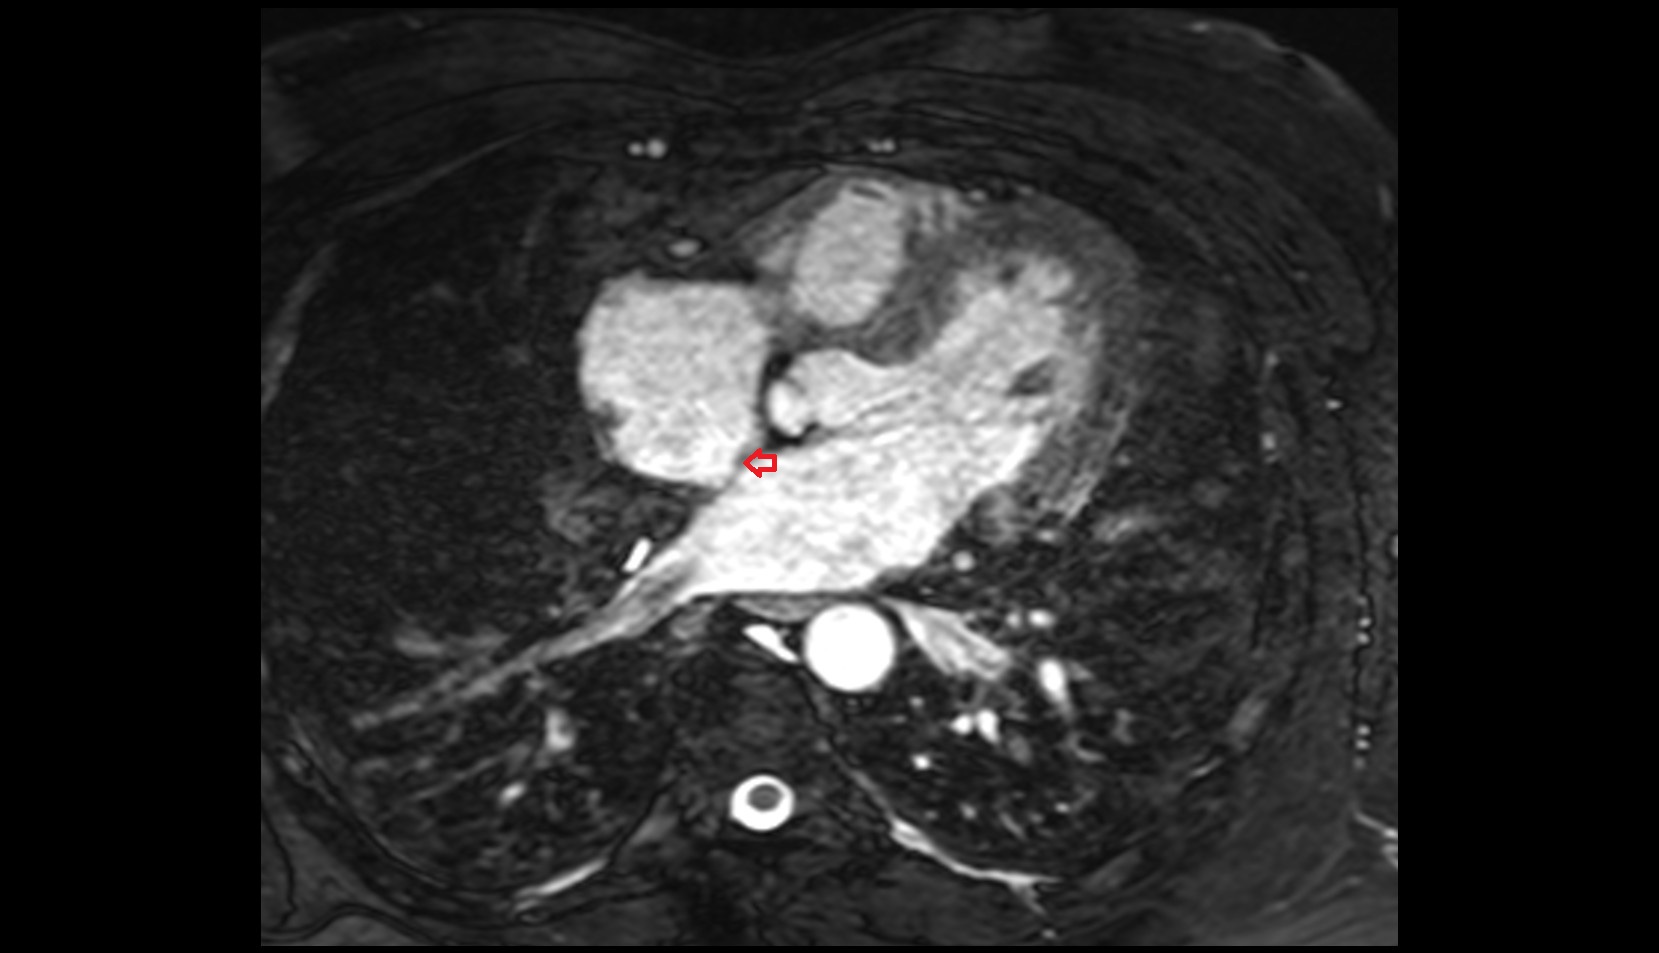

- Heart

- Left ventricle

- Right atrium

- Left atrium

- Right ventricle

- Interventricular Septum

- Left atrioventricular valve (mitral or bicuspid valve)

- Right atrioventricular valve (tricuspid valve)